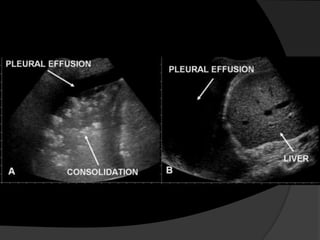

Avaliação Inicial

 Estudos ultra-sonográficos

 Radiografias em decúbito lateral

Toracocentese

 Pode ser realizada à beira do

leito com ou sem o auxílio de

ultrassonografia.

 A realização do procedimento

guiado por ultrassonografia é

indicada se houver dificuldade

na obtenção de líquido pleural

ou se o derrame for pequeno.